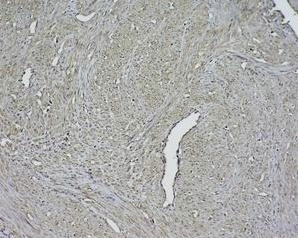

组织/细胞:人宫颈癌;4%多聚甲醛固定和石蜡包埋;

抗原提取:柠檬酸缓冲液(0.01M,pH 6),15min煮沸,用3%过氧化氢阻断内源性过氧化物酶30min;37℃下阻断缓冲液(正常山羊血清)20 min;

孵育:抗β肌动蛋白多克隆抗体,未结合 1:1500,4°C下过夜,然后与二级抗体结合,DAB染色。